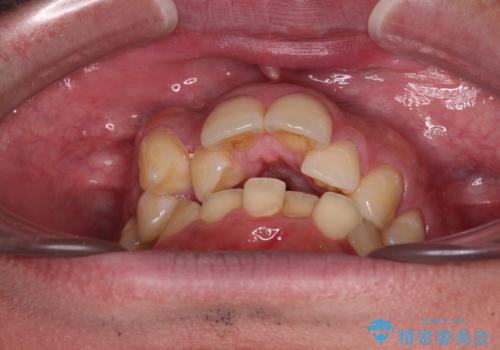

- デコボコと前歯の突出感を気にして来院された患者様です。

舌の突出癖などにより上顎前歯が前方に突出し、さらに歯列幅が狭小になっている状態でした。

上顎歯列幅を側方に拡大するとともに、歯列全体を後方に移動させるためのアンカースクリューと補助装置を使用し、上顎左右第一小臼歯2本、下顎左右第二小臼歯2本、計4本を抜歯し、ワイヤー装置にて矯正治療を行うこととしました。